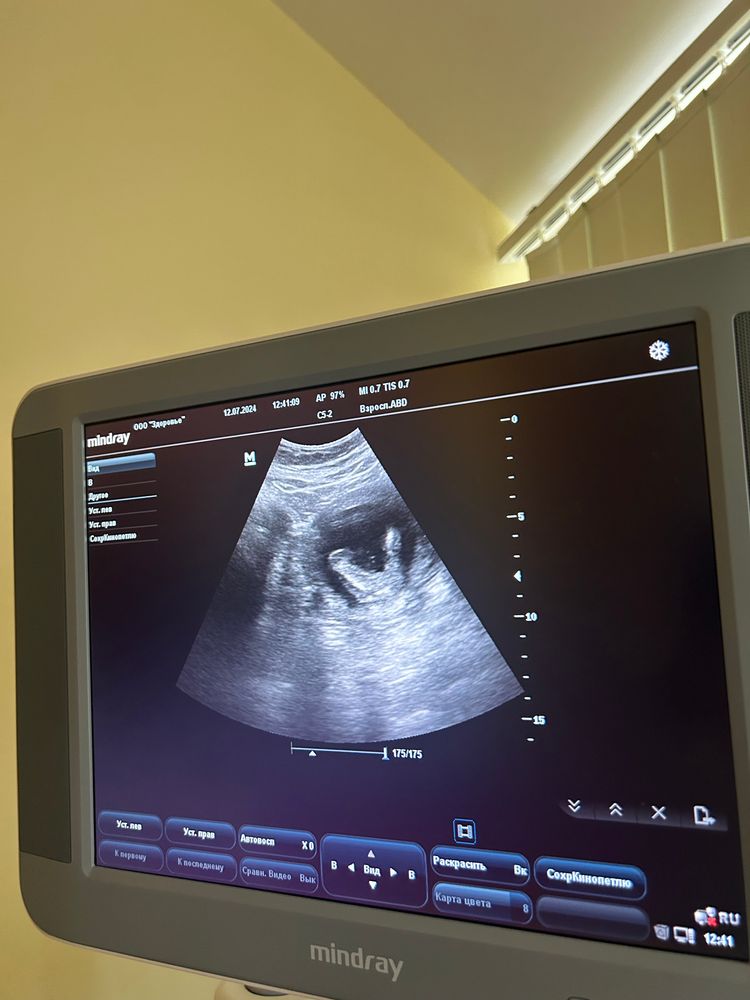

Для сравнения мой мальчик на том же сроке. А у Вас, действительно, похоже на девочку. Изображение

12.07.2024